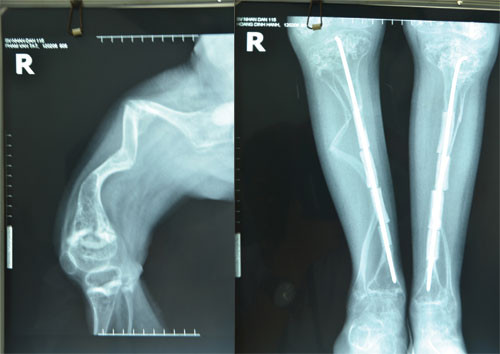

Nhóm nghiên cứu của TS-BS Lương Đình Lâm đã thực hiện một biện pháp táo bạo là cắt nhỏ đoạn xương bị gãy, dùng một dụng cụ tự chế để khoan rộng lòng tủy xương để luồn đinh Rush. Sau đó, phẫu thuật viên sẽ nối các khúc xương đã bị cắt rời thành một đoạn thẳng để vừa có thể giữ vững xương gãy vừa chỉnh lại được tình trạng cong vẹo của tay hoặc chân của bệnh nhân bị bệnh xương thủy tinh. Kết quả bước đầu rất đáng khích lệ, chân các bệnh nhi được phẫu thuật bằng phương pháp này đã được chỉnh thẳng, giúp các em sinh hoạt tốt và giảm đi cảm giác tự ti do bệnh tật.

| Chụp X-quang xương bị cong (bên trái) và sau khi được cắt khúc, chỉnh trục thẳng - Ảnh: do TS-BS Lương Đình Lâm cung cấp |